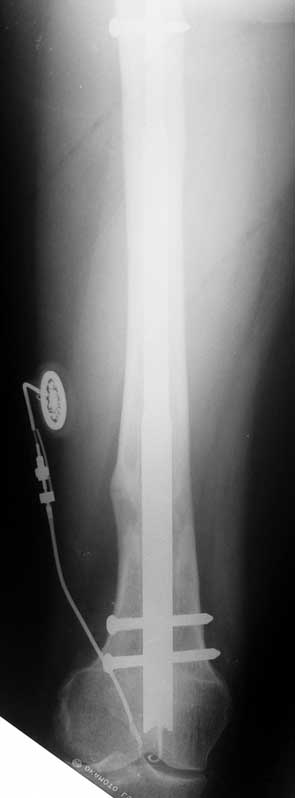

Eksternal fiksatör ile yapılan klasik uzatma tekniklerinin getirmiş olduğu dezavantajları ortadan kaldırarak, hasta konforunu artıran ve enfeksiyon ve hasta kısıtlamasını indirgeyen bir tekniktir.

Tamamen vücut içerisinde kalan bir donanıma sahip, dereceli olarak iki kemik arasında uzatma yapabilmektedir. Üstün teknik altyapısı sayesinde, çivi telemetrik olarak kumanda edilmekte ve hiçbir dış bağlantıya ihtiyaç duymamaktadır.

Hastanın enfeksiyon riskini azalttığı gibi, daha az ağrı duymasını da sağlar ve kozmetik sıkıntılar oluşturmaz. Hastanın daha kısa sürede günlük yaşamına dönmesine ve hastanede de daha az kalması bu teknikle mümkündür. Femur, tibia ve humerus için farklı tipleri vardır.